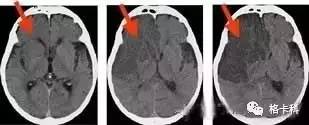

随着时间的推移哽塞面积逐步扩大

脑梗塞的治疗一般采用头部CT、磁共振检查、胸部X光片检查、血液检查、心电图等内科神经学诊疗方法。